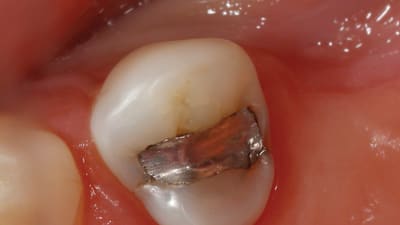

Article Proper Preparation for CAD/CAM Fabrication Bryan Couch, DDS Combining traditional tools with new technology results in optimal patient care October 01, 2015 5 min read